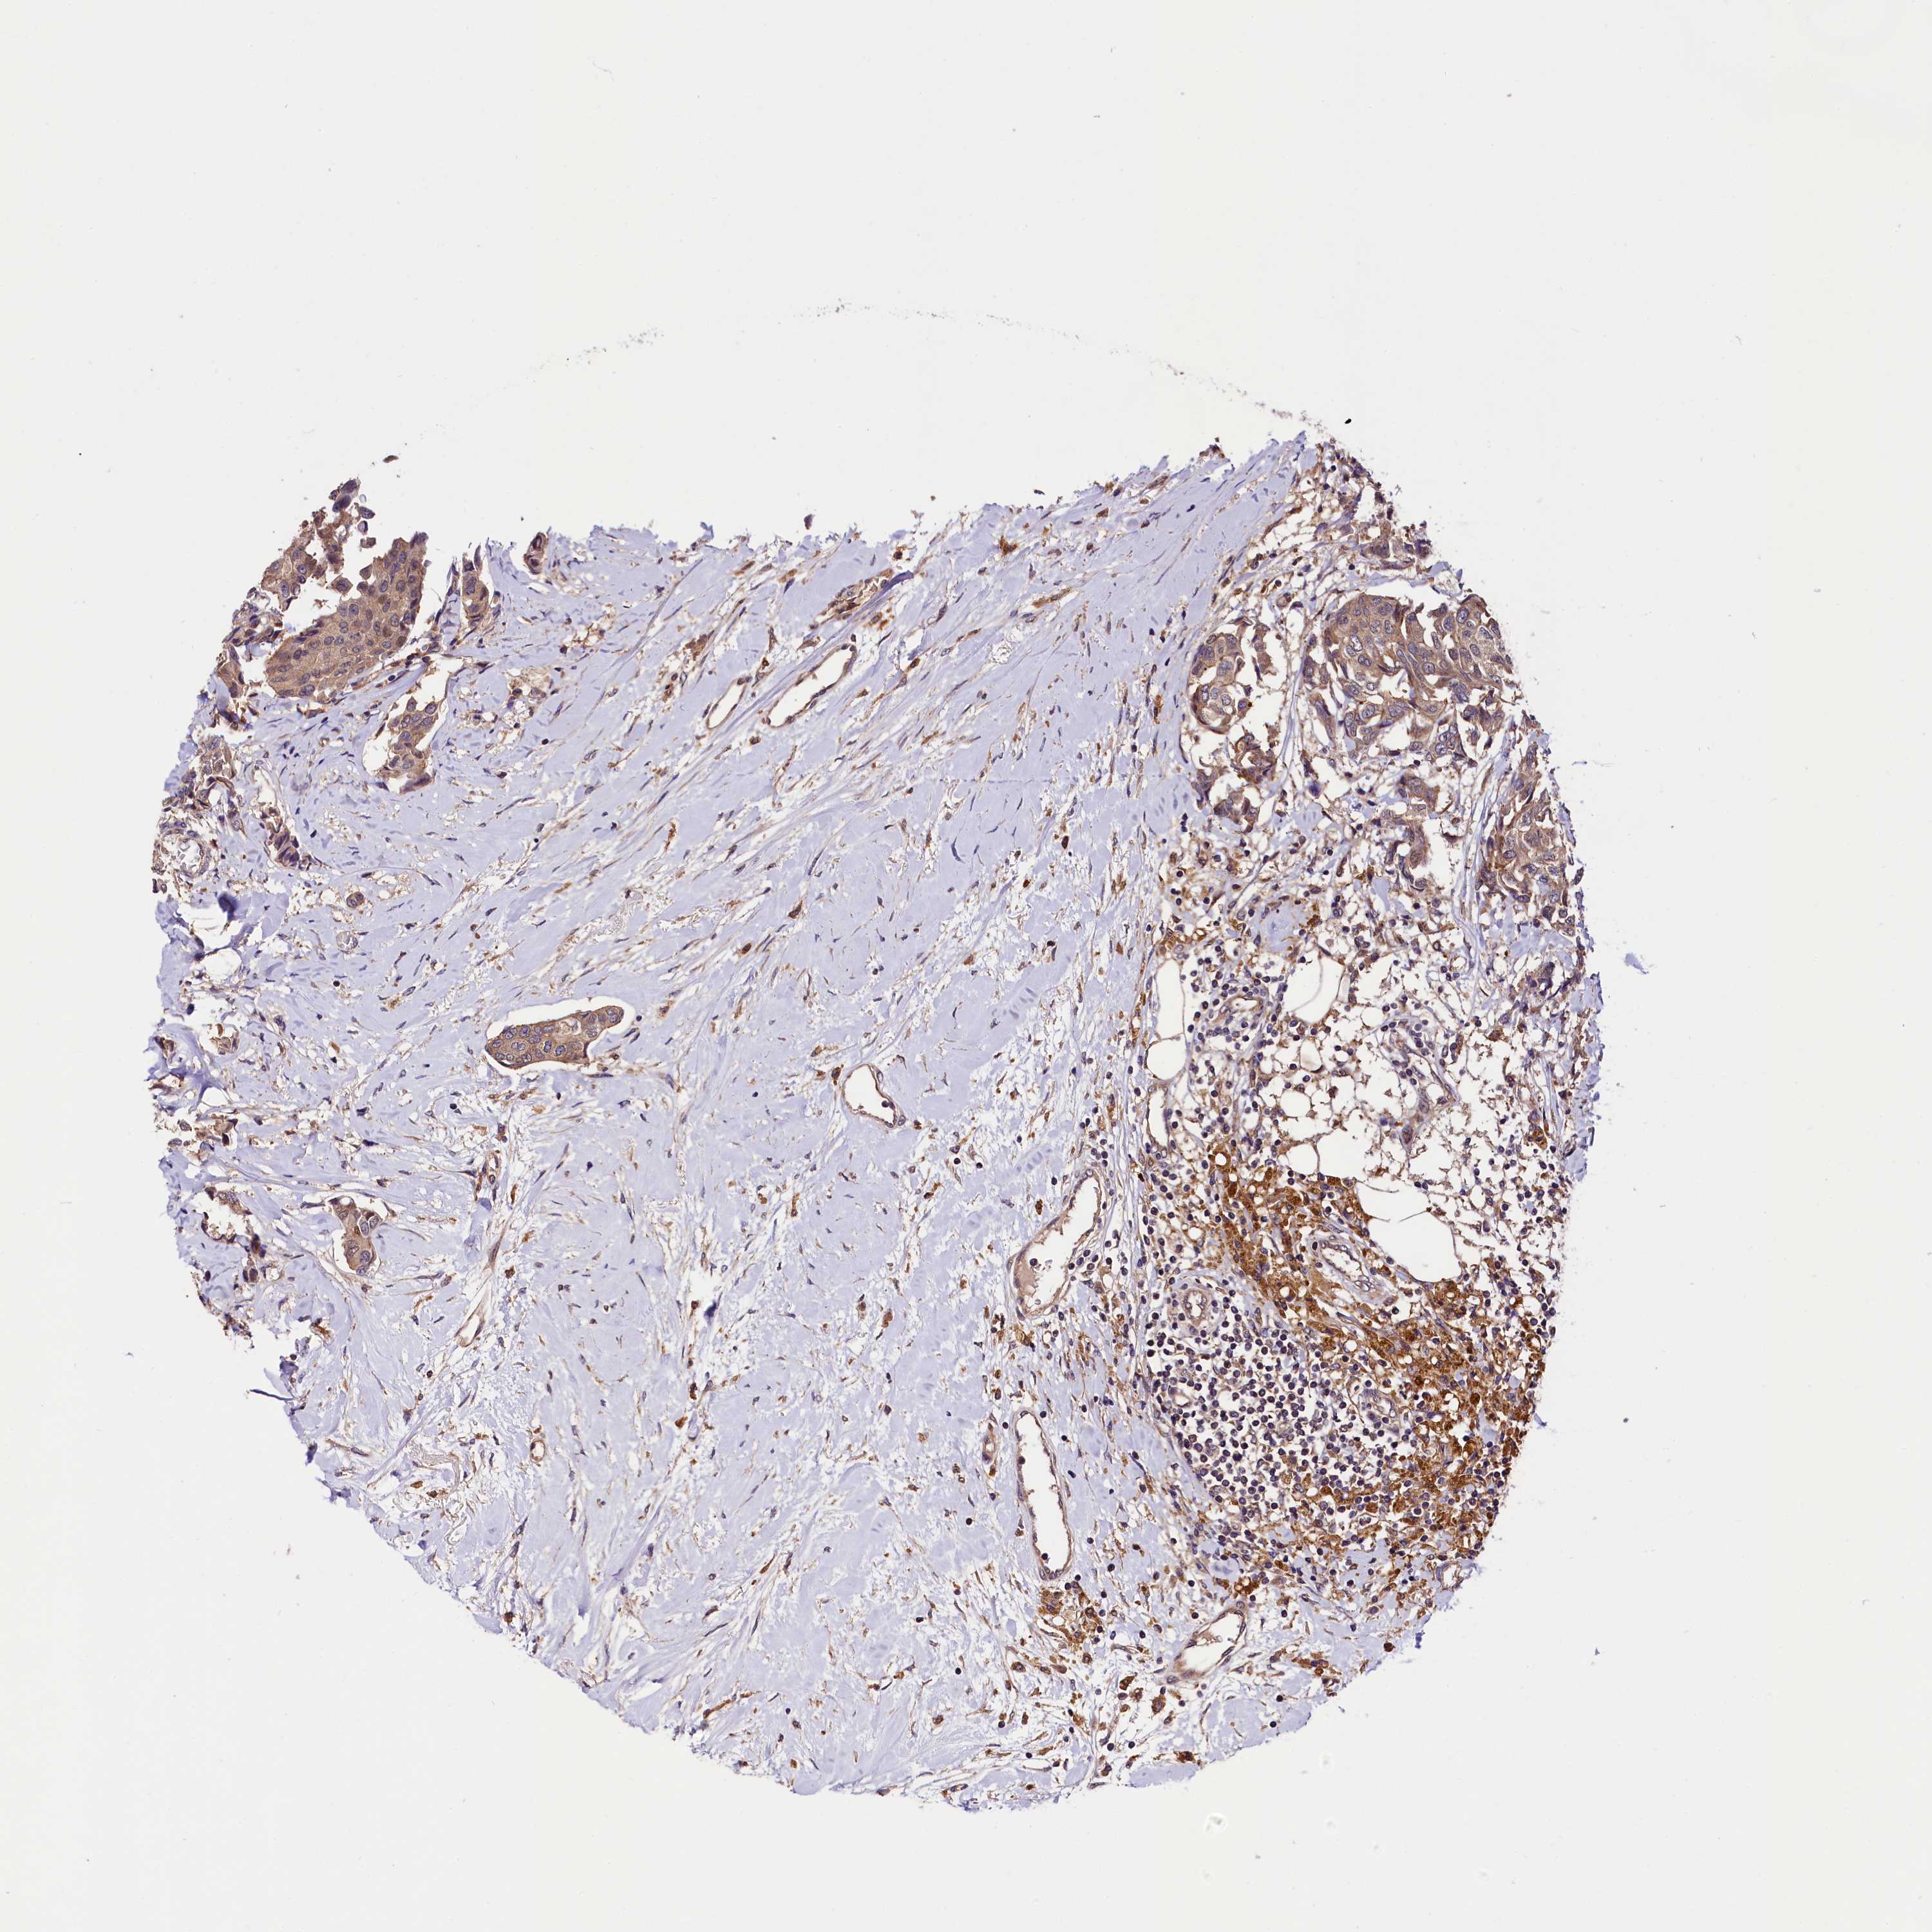

CANCER BREAST CANCER Show tissue menu

BRCA TCGA BRCA VALIDATION PROTEIN EXPRESSION